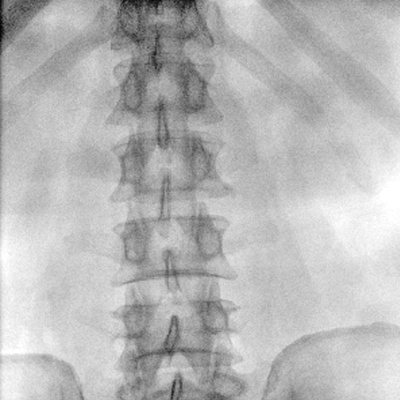

大尺寸動態(tài)平板探測器,高DQE、低噪聲、圖像清晰。采用多分辨率圖像增強(qiáng)處理技術(shù),不同部位不同圖像處理算法,滿足客戶多樣化的需求。

采用智能變頻脈沖透視技術(shù),優(yōu)化圖像質(zhì)量的同時降低輻射劑量,呵護(hù)醫(yī)患健康